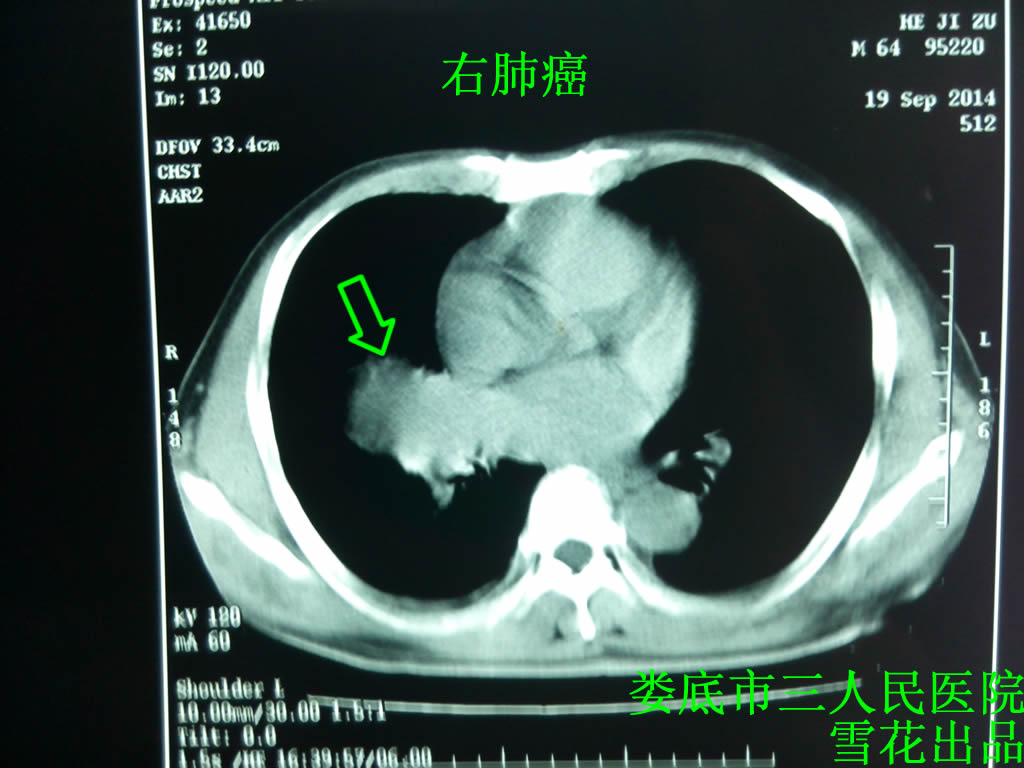

XX,男,64岁,半年前因受凉后出现阵发性咳嗽,咳少量白色泡沫样痰,闻刺激性气味时咳嗽加重,无痰中带血,无畏寒发热,无头痛胸痛。2014.5.26到湘雅二院查CT示:右肺中叶占位性病变,考虑中央型肺癌并右肺中叶不张、纵膈多发淋巴结转移可能性大,建议进一步检查。左上肺多发小结节,性质待定,建议定期复查。左肾上腺肿块性质待定:转移瘤?其他性质?肝脏多发占位性病变,血管瘤?转移瘤?建议进一步检查。行支纤镜检及活检,2014.5.30湘雅二医院病理诊断:(右中肺叶粘膜活检)组织5粒,针头、芝麻大。分化差的癌,因组织挤压严重,需要来我科做免疫组化进一步分类确诊(CKLCACD56CK7CK5/6CK18Ki-67TTF-1)协助诊断。2014.6.6补发免疫组化检查后:(右中肺粘膜活检)组织5粒,镜下见分化差的肿瘤免疫表型:CK+),LCA(-)CD5/6(-)CK7(-)CK5/6(-)Ki-67(>50%+)CK18+),支持高级别神经内分泌肿瘤:肺小细胞肺癌。湘雅二院考虑患者右肺小细胞肺癌肺内、肝、肾上腺转移,广泛期,已到非常晚期,谨慎推荐化疗,患者及其家属拒绝,给予对症支持治疗出院,出院后患者咳嗽、胸痛气促症状进行性加重,20148月无明显诱因出现痰中带血,并逐渐转变为咯血,活动后气促明显,为求治疗于2014.9.19第一次入住我科,查肺部CT示:肺癌治疗后复查,与2014.5.26日外院片对比,右肺中叶软组织肿块较前稍进展,左肺上叶新见小结节影,建议追踪观察(见图一)。B超示肝、肾上腺转移可能。2014.9.20立即给予TEP方案化疗(紫杉醇90mg d18  VP-16 0.15 d1-3 顺铂40mg d1-3,化疗前3天患者无明显化疗反应,但仍然咳嗽、痰中带血、胸痛气促,查舌象舌红苔白,脉弦数,根据祖国医学考虑肝郁化火、迫血妄行、肝火犯肺,给予疏肝散加减方口服疏肝理气、凉血止血、清肺止咳,具体见下: